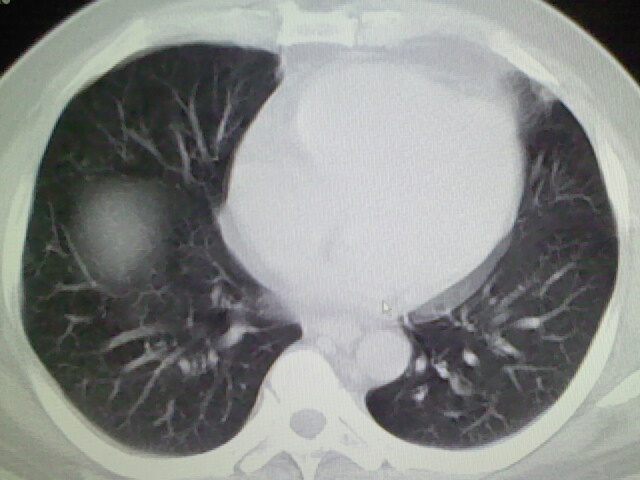

标题: CT17932:临床怀疑肺栓塞

男,34岁,自觉右侧胸痹,胸闷3天余

右侧肺动脉似见密度稍低影,请在机器的薄层上再看看有没有充盈缺损。

左上肺局限性肺透光度减低,肺纹理稀少;这虽然符合早期肺栓塞的改变,但与局限性肺气肿难以鉴别。

书上讲早期肺栓塞就是表现肺透光度减低,肺纹稀少。